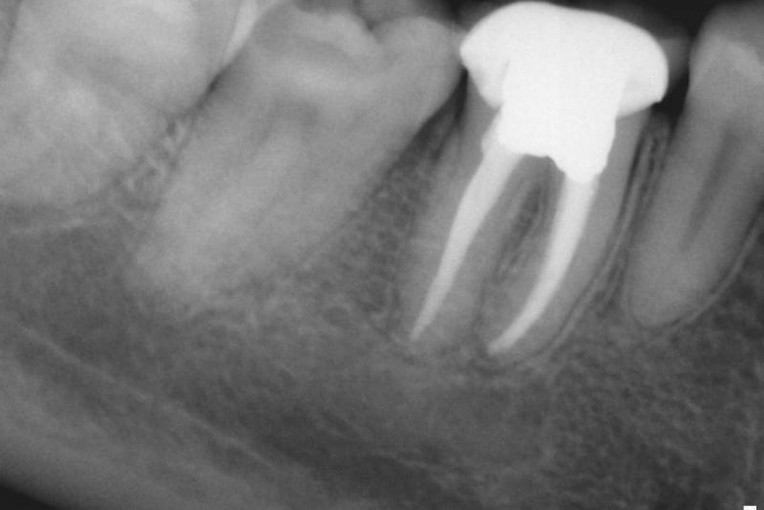

Before your root canal, your dentist will assess your dental health and take X-rays to determine the extent of the infection. It’s common to experience some anxiety about the procedure, but modern dentistry has made root canals much more comfortable than in the past. Your dentist may discuss options for sedation or local anesthesia to ensure a pain-free experience.

With proper care, a root canal-treated tooth with a crown can last for many years, often 10 to 15 years or even longer. The crown protects the tooth from fractures and further decay, ensuring its longevity. Regular dental check-ups, good oral hygiene, and avoiding habits like chewing ice or hard candies can help maintain the strength and function of the restored tooth.

Before the procedure, you may experience pain, swelling, or sensitivity in the affected tooth. After the treatment, these symptoms usually subside within a few days, leaving you with a stronger and healthier tooth. Crowns or permanent fillings help restore both the appearance and function of your teeth, giving you confidence in your smile.